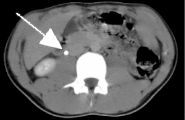

Right image is a curved coronal reconstruction urogram clearly showing partial obstruction with a dilated right ureter and collecting system (arrow) proximal to the stone.

This is performed on an Advanced 4D Silicon Graphics Workstation to produce "IVP-like" coronal sections depicting the course of the ureters as shown in the top right image.